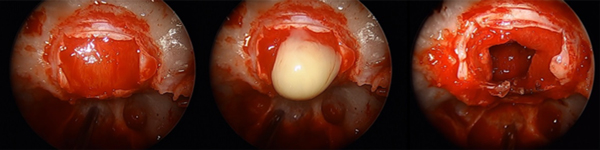

Se realizó abordaje endoscópico transnasal transesfenoidal (ver video). Luego de la durotomía selar, se evidenció salida de material amarillento, purulento, a presión (Fig. 2). Se evacuó todo el contenido y se resecaron las paredes de la lesión. El extendido intraoperatorio fue compatible con craneofaringioma.

Figura 2. A: Durotomía selar. B: Material purulento. C: Lecho quirúrgico luego de la resección de la lesión.